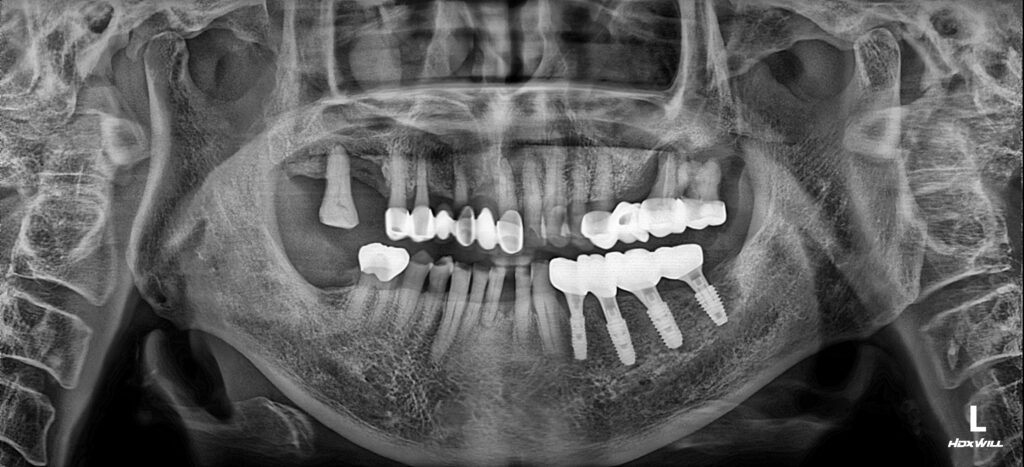

26.02.23

4개의 임플란트를 식립 후 마무리한 모습입니다 ! 상악의 치아들이 브릿지 보철물로 제작되어 있었으나, 만약 더 늦게 아래 치료를 진행하셨다면 상악에 있는 치아들이 내려오는 ‘정출’이라는 현상으로 치료가 더욱 어려울 수 있었습니다.

남포동임플란트 서울 화이트S치과는 단단하고 안정적인 임플란트 식립뿐만아니라 정밀한 교합을 맞춰드리므로써, 자연치아와 같은 편안함을 느끼실 수 있도록 도와드렸습니다.

또한 계속관리가 필료하신 부분들을 놓치지 않고 받으실 수 있도록 환자분 일정에 맞는 예약일정을 잡아드려서 너무 만족해하셨어요:)